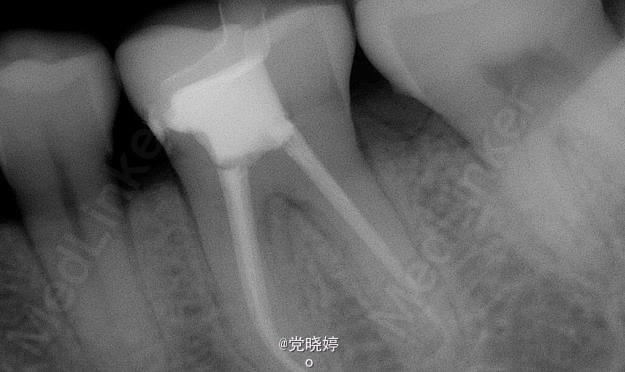

36根管再治疗后E.max瓷嵌体修复

患者,女,30岁,36牙根管再治疗后要求嵌体修复。平素体质一般,无心脏病、高血压等病史,无药物、食物过敏史。

36根管再治疗之后嵌体修复